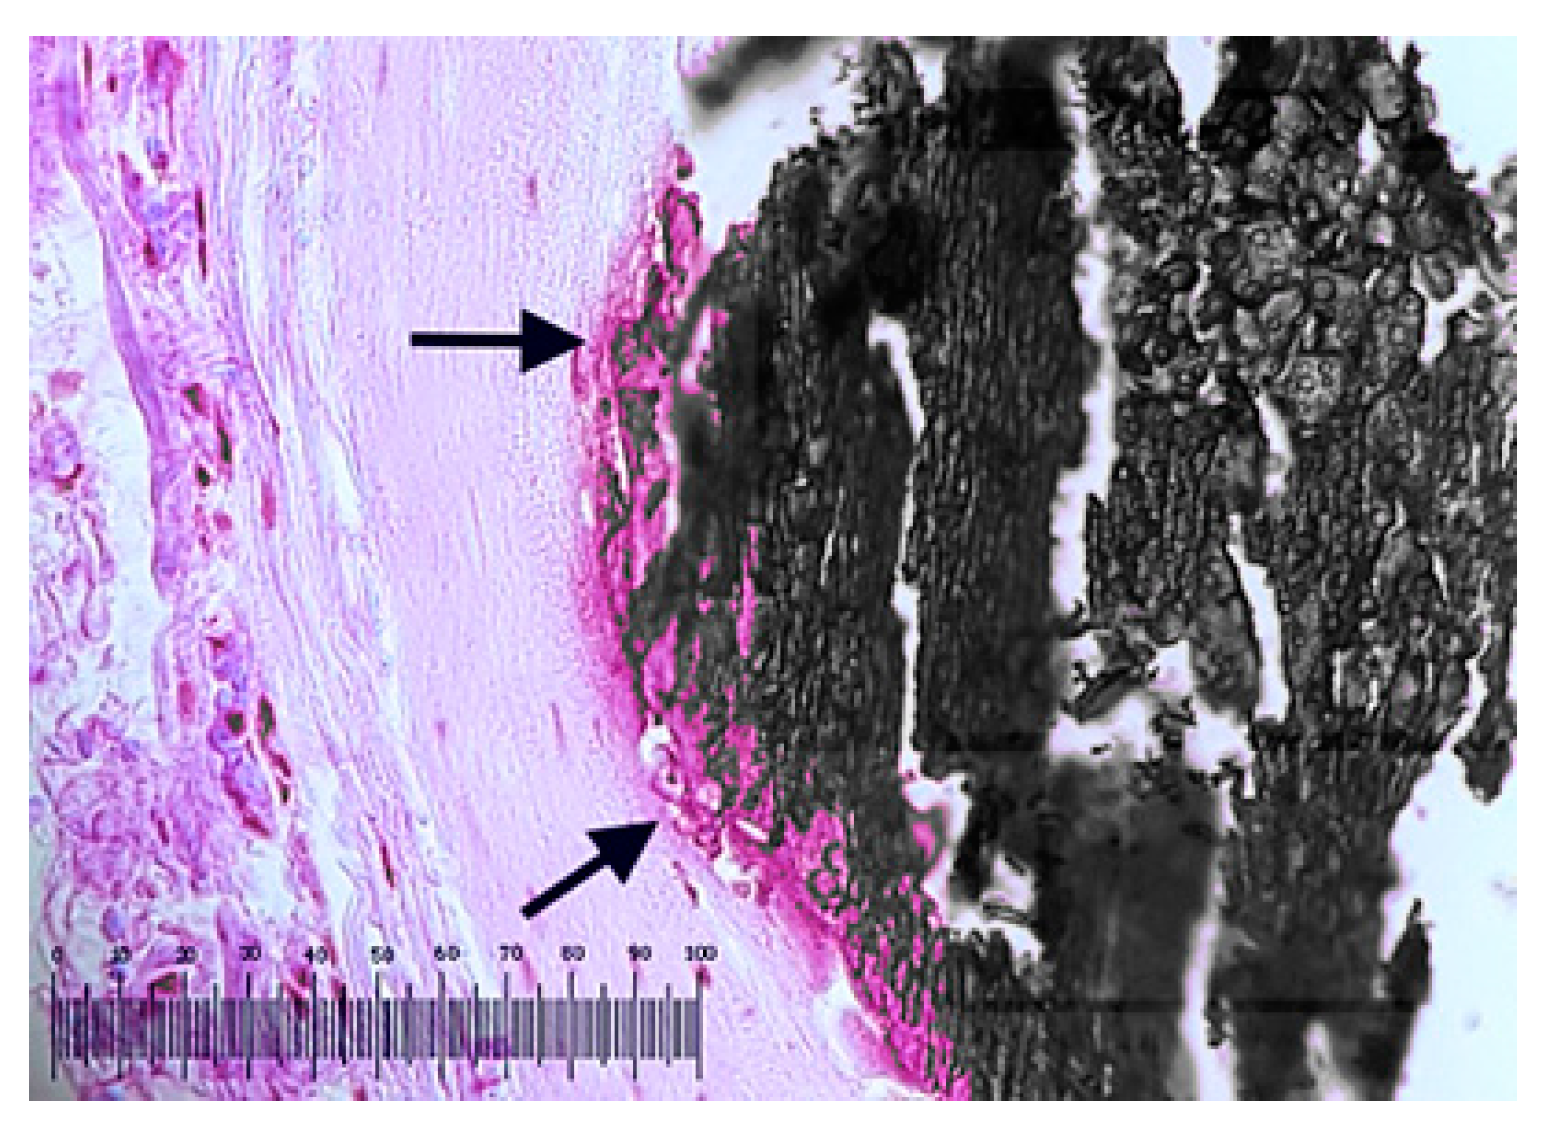

For sample P14 a cross section of coronary artery (Figure 15a) indicates the concentric narrowing of coronary lumen by the proliferation of endothelial cells approximately 70% (N). There is also an area of calcification outside the sent—possibly the old calcified atheroma plaque (C) that produced the initial stenosis of the artery. In the cross section, the absence of metal turns in the stents is observed in the area marked with *, possibly due to fracturing processes following the pressure exerted by the calcified area.

Figure 15.

Cross section of RCA for: (a) sample P14 showing 70% ISR (N) and calcified atheroma plaque (C) can be observed. Arrows show stent struts and the absence of stent struts is indicated by the asterisk (*); (b) sample P18 with peripheral calcifications (C) compressed behind the stent threads and the arterial lumen almost completely restenosed (N).

For sample P18 (Figure 15b) the sectioned tissue shows compressed peripheral calcifications (C) behind the stent threads and the almost completely restenosis of the arterial lumen (N).